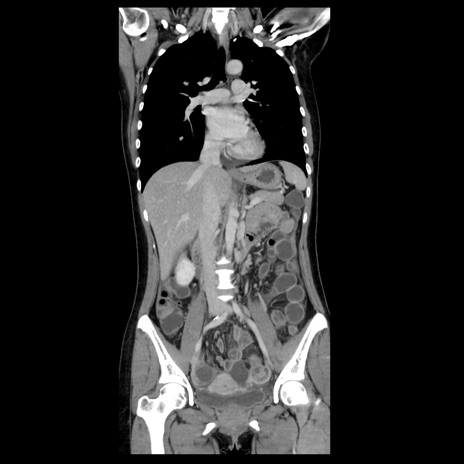

症例39(冠状断像)

【症例】40歳代女性

【主訴】上下腹部痛

【現病歴】2日目から下腹部痛あり。夜間は痛みで眠れなかった。昨日より上腹部痛と下痢が出現。臥位で痛みは軽快したため、休んでいた。本日になって臥位でも立位でも痛みが強くなってきたため救急要請。

【既往歴】子宮内膜症

【身体所見】部:平坦・軟、左上下腹部に圧痛あり、反跳痛あり。

【データ】WBC 21800、CRP 26.78

CT